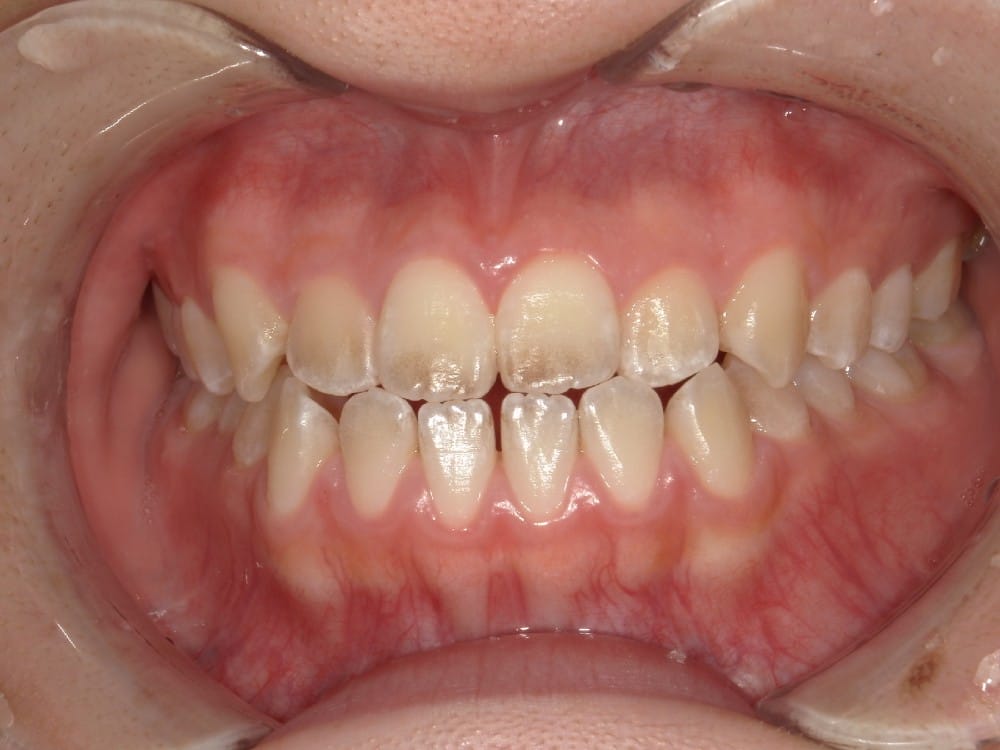

この子は、中学生の女の子で、受け口、横顔が気になるとのことでご来院されました。

治療前の様子

分析をしますと

- 骨格的な上下あごの前後差は中等度

- 噛み合わせの位置も下あごの奥歯が半分くらい前にズレていた

- 上の前歯が前に傾斜、下の前歯が内側に傾斜しているにもかかわらず、受け口

というケースで、外科的な処置も検討するようなケースでした。

患者さまに外科的な手術の選択肢も提示しましたが、希望されず、横顔の変化はおそらく起こらないことを納得の上、治療をスタートいたしました。